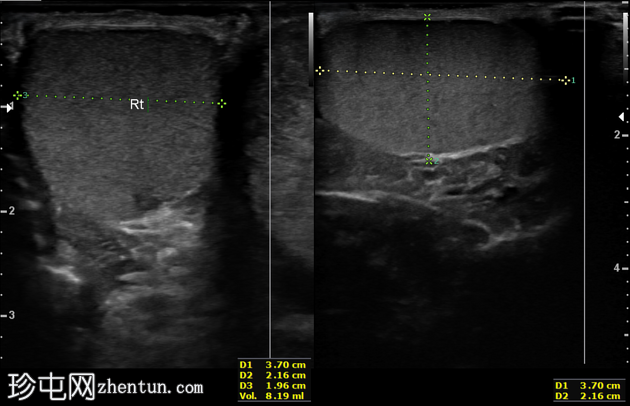

左侧睾丸及附睾肿大,呈低回声,内部回声不均匀。彩色多普勒未见血流信号。左侧精索可见漩涡征。

左侧睾丸体积约10 cm³,伴轻度左侧鞘膜积液。

右侧睾丸外观正常,血流信号清晰。